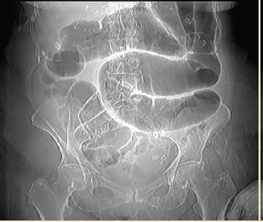

Paciente del sexo masculino, de 76 años, quien inició padecimiento actual hace 72 horas, con presencia de distensión y dolor abdominal opresivo 8/10 por “escala visual análoga” detonado por ingesta, sin presentar evacuaciones ni canalización de gases. Refirió tratamiento sintomático con antiespasmódicos, antiácidos y medicación local transrectal (supositorio), sin mejoría. Como antecedentes relevantes menciona patrón intestinal anormal con tendencia a la constipación crónica. A la exploración física dirigida, abdomen prominente a expensas de distensión de asas intestinales, peristaltismo disminuido con ruidos hidroaéreos, timpánico a la percusión con características metálicas, doloroso a la palpación superficial y media, con hiperalgesia e hiperbaralgesia, signo de rebote dudoso, tacto rectal con ámpula rectal vacía. Se realizaron radiografías posteroanterior de tórax y anteroposterior de abdomen identificando colon sigmoides redundante con aumento del patrón de distribución aérea, la cual ocasionó sobreposición de asas sobre el ángulo hepático y esplénico, presencia de material de residuo en íleon y colon ascendente, así como edema interesa (figura 1 y 2).

Figura 1 AP de tórax. Aumento del patrón de distribución aérea en marco colónico, sobreposición de asas sobre ángulo esplénico y hepático

Figura 2 AP de abdomen. Colon sigmoides redundante, gran aumento del patrón de distribución aérea, sobreposición de asas sobre marco colónico, ángulo hepático y esplénico, imagen en grano de café